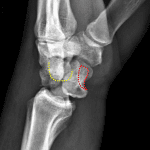

- Acute lunate dislocation with 90 degrees volar tilt and 1 cm volar displacement of the lunate

- Tiny ossific densities project along the dorsal aspect of the proximal carpal row

- Soft tissue swelling about the wrist

Acute lunate dislocation with 90 degrees volar tilt and 1 cm volar displacement of the lunate.

Tiny ossific densities project along the dorsal aspect of the proximal carpal row, which may represent tiny chip/avulsion fractures. No additional fracture identified.

Soft tissue swelling about the wrist.